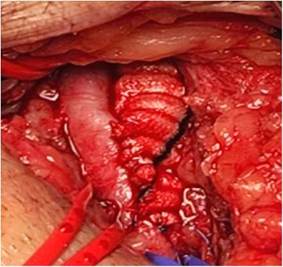

Figura 2: Aneurisma iliaco izquierdo en el tranquirúrgico, vemos en la primera imagen integro y en la segunda evidenciamos el contenido. Autoría propia.

Se presenta el caso de un paciente masculino de 75 años de edad, que acude al servicio de emergencias del Hospital obrero N°2 de la Caja nacional de Salud, Cochabamba, con un cuadro clínico de más o menos 3 semanas de evolución, caracterizado por presentar dolor lumbar de inicio súbito, secundario a realizar esfuerzos grandes, debilidad en miembros inferiores, astenia, adinamia y mareos. Antecedentes: Insuficiencia cardiaca, enfermedad de Chagas, bloqueo auriculoventricular grado 3 y portador de marcapasos hace 20 años. Al examen físico regular estado general, consciente, orientado, afebril, hemodinámicamente estable, al examen físico regional sin particularidades. Laboratorios dentro de parámetros normales. Se le realiza exámenes complementarios: Ecografía abdominal que reporta un aneurisma fusiforme de la arteria iliaca común izquierda, trombosis mural aneurismática de evolución subaguda, que compromete el 50% de la luz aproximadamente y una tomografía Abdominal con contraste donde se evidencia aneurisma bi-iliaco, con diámetros de arteria iliaca izquierda (64 mm) y derecha (35 mm), que se extiende la bifurcación de la iliaca sin datos de disección ni sangrado. Paciente es transferido al servicio de Cirugía, donde se le propone cirugía y el paciente acepta. Se le realiza como tratamiento quirúrgico una derivación aorto-bifemoral con una prótesis de dacrón, por un abordaje transabdominal. Pasa a salas de terapia intensiva, donde como tratamiento médico se le da soporte con fluidoterapia, analgésicos, profilaxis antibiótica y anticoagulación, evolucionando favorablemente. El décimo segundo día postoperatorio se realiza ecografía de control, donde se evidencia permeabilidad de la prótesis, pasando a salas generales. Es dado de alta el décimo quinto día postoperatorio.

En nuestro caso se optó por una cirugía abierta por los diámetros de los aneurismas, ya que era bilateral se escogió un abordaje transperitoneal y no retroperitoneal, ya que el mismo facilita la visualización y el procedimiento. Se requirió de un cirujano cardiovascular, cirujano vascular periférico y cirujano general. Encontramos actualmente un reporte de caso en Madrid-España del año 2025, donde a pesar de tener diámetros mayores a 3.5cm en los aneurismas aorto bi-iliaco, ya se está optando por tratamientos netamente endovasculares complejos exitosos4,9. Que difiere de lo publicado en el 2020 en la Revista Médica del Instituto Mexicano del Seguro Social, donde reportan que los tratados de forma endovascular como complicaciones presentaron claudicación, isquemia colónica e isquemia de médula espinal. Además, que a comparación de la cirugía abierta presentaron mayor probabilidad de oclusión o fuga, por lo cual la cirugía abierta sigue siendo buena opción, y fue la que escogimos en nuestro paciente5.